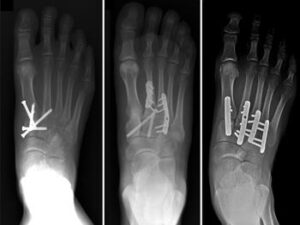

Various methods of internal fixation can be used to fix Lisfranc injuries depending on the injury pattern. (Left) Multiple screws can be used. (Center) A combination of plates and screws are sometimes required when fractures are present in addition to a torn ligament. (Right) Plates that span the joints are also an excellent method of fixation.